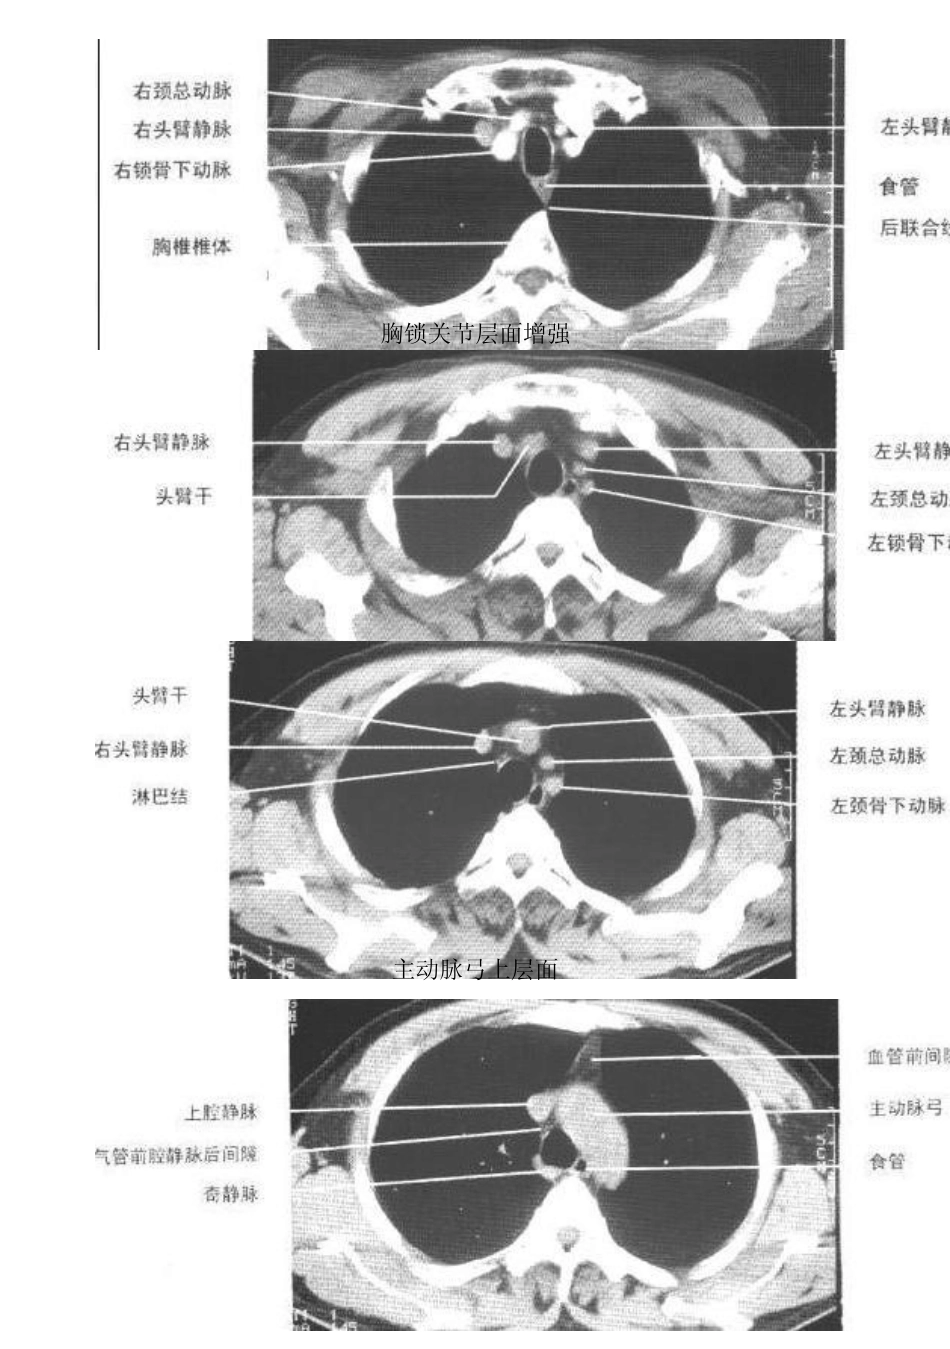

胸部CT图谱

1 胸部CT 图谱 胸锁关节层面平扫 2 胸锁关节层面增强 主动脉弓上层面 3 主动脉弓层面气管分叉层面平扫气管分叉层面增强 肺动脉干与右肺动脉层面平扫 4 左心房层面平扫左心房层面增强左、右心房层面增强 5 四腔心层面平扫心室层面平扫 6 7 8 9